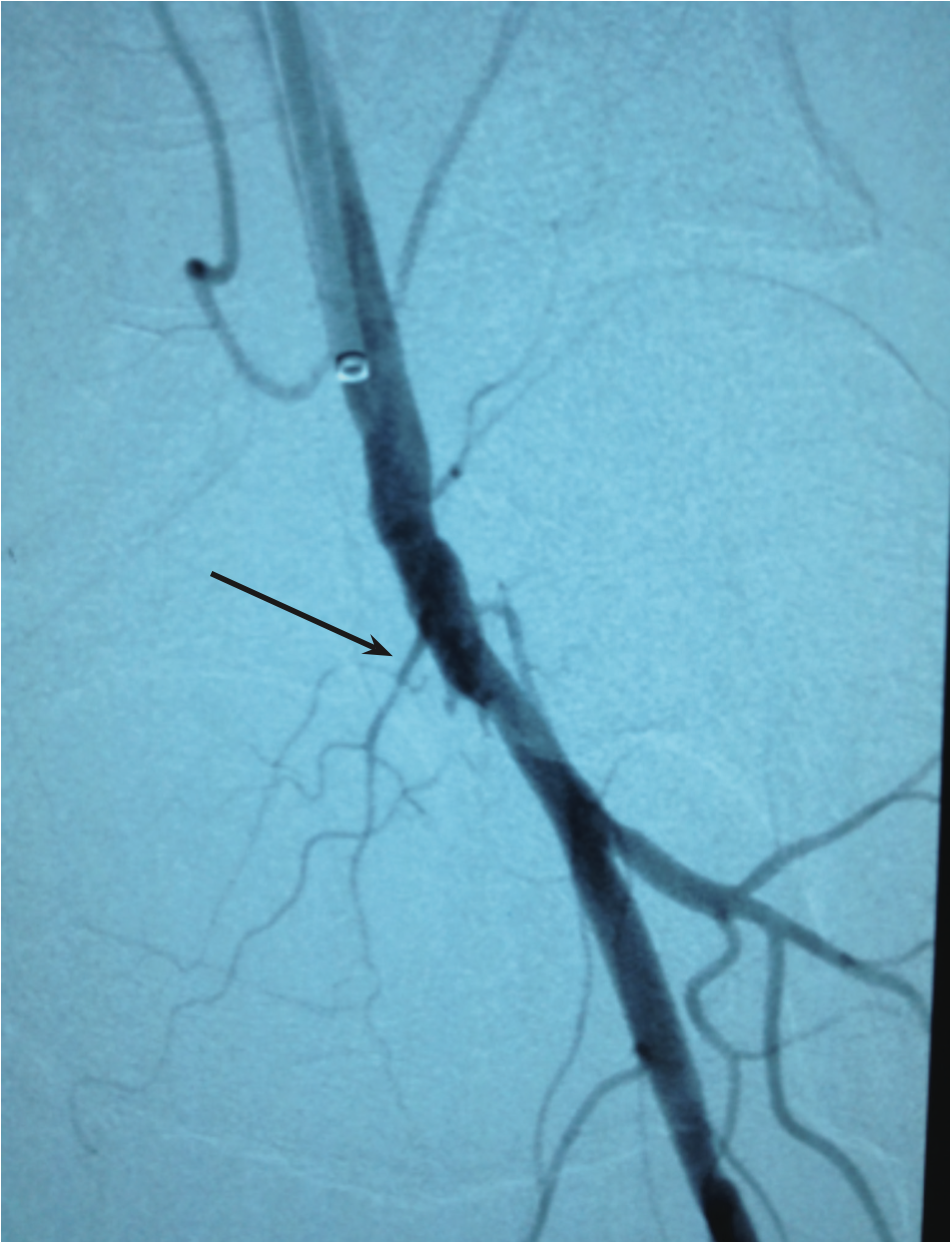

The 5 Fr system was exchanged for a 7 Fr 0.038-inch x 90 cm Flexor Check-Flo Raabe sheath (Cook Medical). Angiography confirmed flush occluded left SFA at its ostium (note arrow in Figure 1). We advanced a 0.035-inch x 260 cm Advantage glidewire with a 5 Fr angled-tip Glide catheter support and crossed half way down the occluded SFA. At this point, we were subintimal and could not advance any further (note upper arrow in Figure 2).

While maintaining the Runthrough NS wire in position, we advanced a 0.014-inch x 300 cm Spartacore guide wire (Abbott Vascular) from the right CFA with a Quick-Cross support catheter. We carefully navigated the wire through the entire length of the SFA into the left popliteal artery and distally into the left anterior tibial artery. At this point, we deployed four self-expanding 6 mm FlexStents (Cordis) in an overlapping fashion, measuring 380 mm in length, extending from the left distal SFA all the way up to the left SFA ostium at the level of the CFA (Figure 6). We performed final balloon angioplasty to expand the stent struts with a 5 mm x 220 mm Savvy balloon (Cordis). Final angiography showed excellent results with good distal flow (Figure 7).